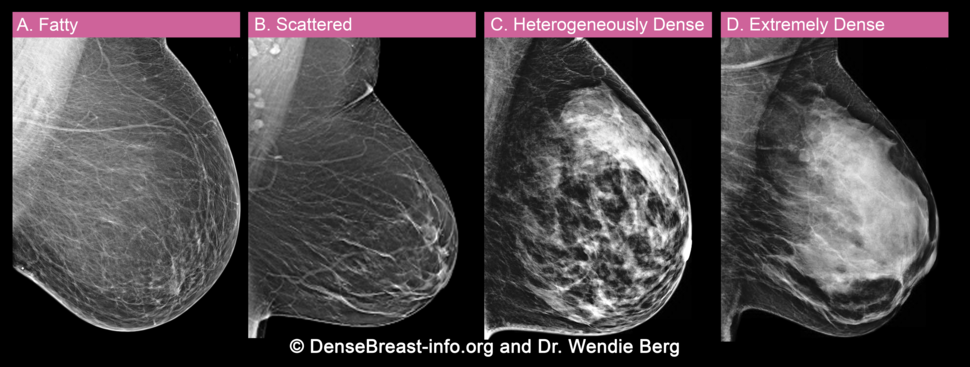

They appear as white spots or flecks on a mammogram but can't be felt during a breast exam. A new group has formed. For women treated for breast cancer in the past, calcifications may also be due.

There are numerous causes for calcium deposits in the breasts, including: But, japanese food natto has the ability to decalcify and maintain uniform level of calcium throughout the body and parts. Breast calcifications. california pacific medical center: